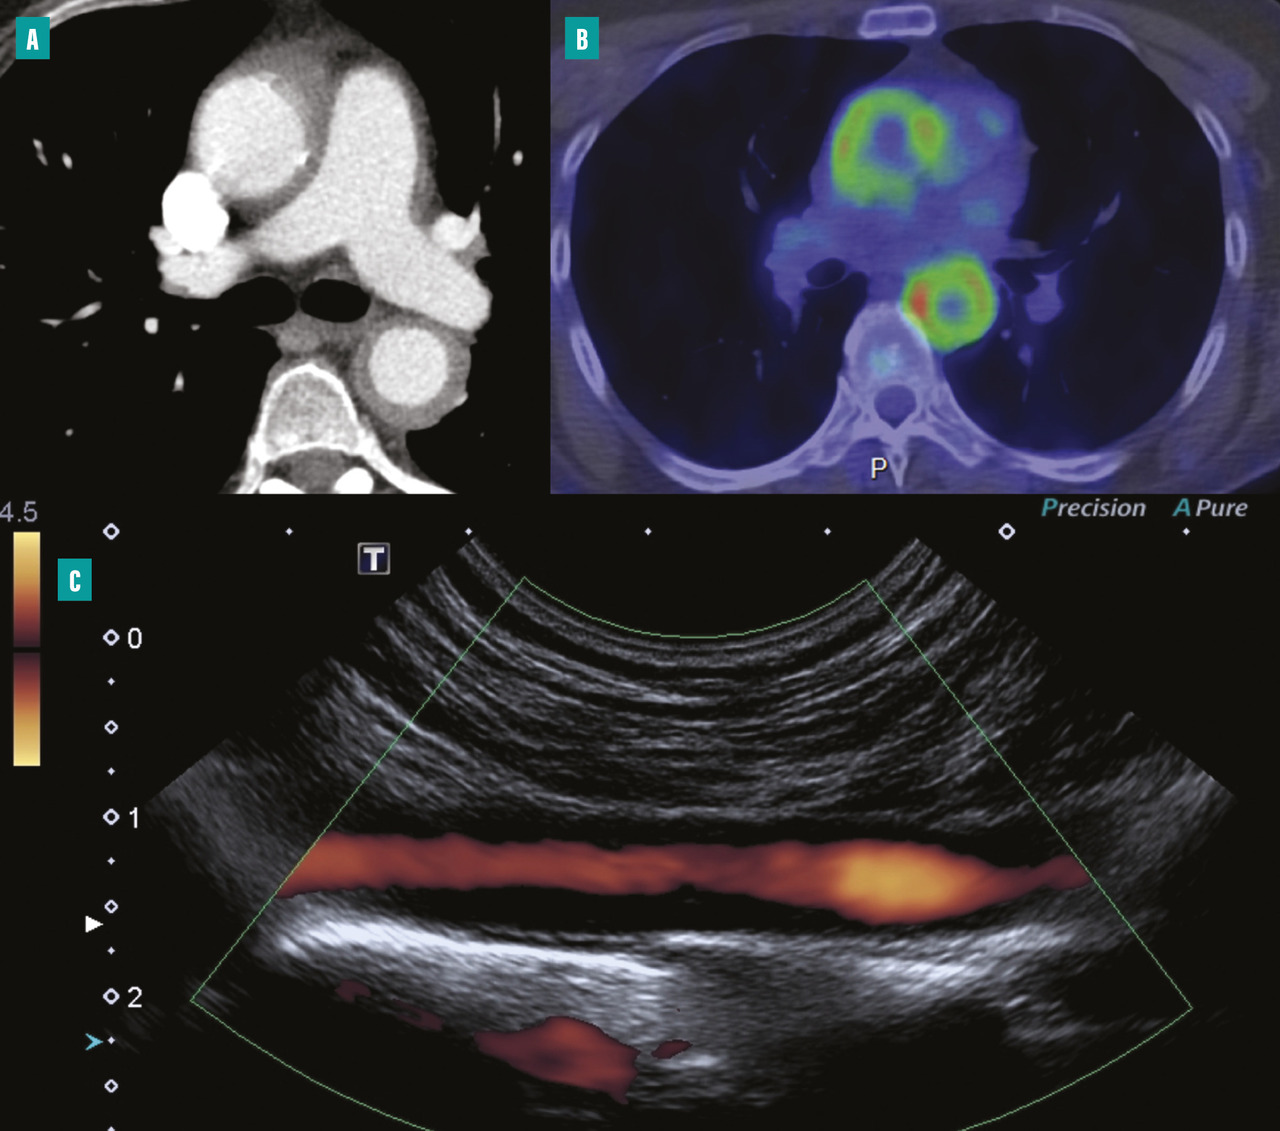

L’échographie-Doppler artérielle est un examen non invasif de première intention permettant d’explorer les artères des membres et les troncs supra-aortiques.15 Elle peut mettre en évidence un épaississement circonférentiel et homogène de la paroi artérielle, une sténose artérielle et son éventuel retentissement hémodynamique d’aval, une occlusion artérielle ou un anévrisme (fig. 2 ).

Par rapport à l’échographie-Doppler artérielle, l’angioscanner artériel a l’avantage de pouvoir explorer la portion thoracique de l’aorte. À la phase aiguë inflammatoire, on peut observer un épaississement pariétal supérieur à 3 mm, parfois une prise de contraste pariétale qui correspond à un rehaussement homogène au temps tardif de l’injection.16

Tomographie par émission de positons au 18F-FDG

La tomographie par émission de positons au 18-flurodésoxyglucose (TEP 18F-FDG) a un intérêt dans le diagnostic de la maladie, notamment dans la phase active, afin d’affirmer le caractère inflammatoire d’une aortite et la localisation précise des segments atteints, notamment chez des patients porteurs d’une forme clinique fruste. La fréquence de l’atteinte artérielle en TEP oscille entre 35 et 60 % des patients selon les études.16

Dans le suivi, elle constitue également un argument supplémentaire à l’évaluation de l’activité de la maladie en cas de positivité, toujours à confronter à l’évaluation clinique et biologique du patient.